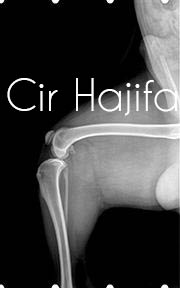

Dne 25.1.2015 byly odborně udělány rentgeny DKK a pately na veterinární klinice v Jesenici díky blížící se bonitaci v Dětřichově. Výsledky dopadly skvěle: DKK(HD) A/A, ED 0/0, pattela - negativní, Entropium - negativní, Endropium - negativní, Distichiáza - negativní. Výška: 55 cm Váha: 25.7 kg |